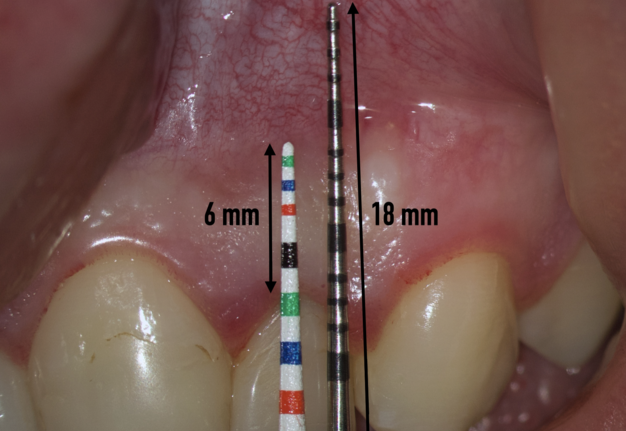

Therefore, the selection of this type of incision requires thorough treatment planning [12]. To avoid the incision falling into an existing bone defect or a defect created by an osteotomy, it is rational to plan a submarginal incision. We can determine whether we can make it, according to the clinical situation of a patient by following approach. To do this, first we need to determine on the CBCT where the bone defect is located or where the osteotomy will take place. Then, using a virtual ruler, measure the distance from the incisal edge of the tooth on which the intervention will be performed to the beginning of the bone defect or osteotomy (Fig 7).

We transfer this distance is transferred to a metal probe and fixed with an endodontic stopper. Next, we take a plastic probe and substitute it near the zenith of a tooth on which the intervention will be performed at a mark of 6 mm (3 mm must be retreated to perform a submarginal incision and another 3 mm is needed for the formed flap to overlap healthy bone tissue) (Fig 8).

We compare the lengths of the plastic and metal probes. The first option is when the metal probe is above the plastic one, then we can assure that the incision and the Ochsenbein-Luebke flap will accurately cover the bone defect and the submarginal incision is safe (Fig 9).